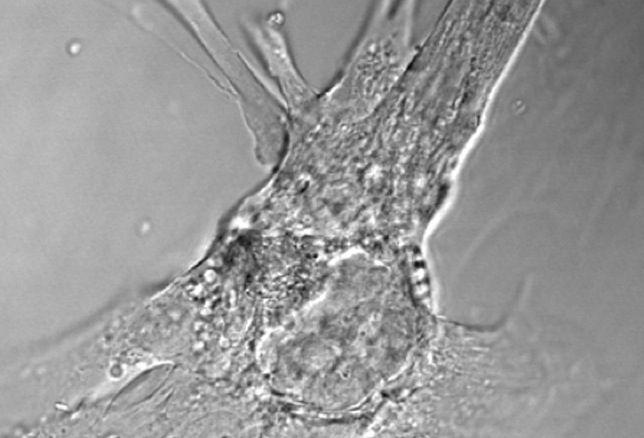

Los cardiomiocitos son células del miocardio capaces de contraerse de forma espontánea e individual que hacen que el corazón lata

Después de un infarto, las células cardiacas quedan seriamente dañadas debido a la privación de oxígeno que se ha producido tras la lesión y no pueden funcionar correctamente, explica Srivastava. Hasta hace poco se pensaba que este daño no podría ser reparado; sin embargo Srivastava y sus colegas ya habían demostrado que era posible reprogramar estas células a través de tres factores de transcripción, que inducen la conversión de los fibroblastos cardiacos, que constituyen la mitad de las células del corazón de los mamíferos, a cardiomiocitos.

En el presente estudio, los investigadores han empleado el mismo método para reprogramar las células del corazón y han visto que funciona: las células dañadas de los ratones se convertían en cardiomiocitos. Prueba de concepto En su opinión, «estos experimentos en ratones son una prueba de concepto de que es posible reprogramar células no funcionales en otras que capaces de hacer latir al corazón y ofrecen una vía innovadora y menos invasiva para restaurar la función cardiaca después de un ataque al corazón».